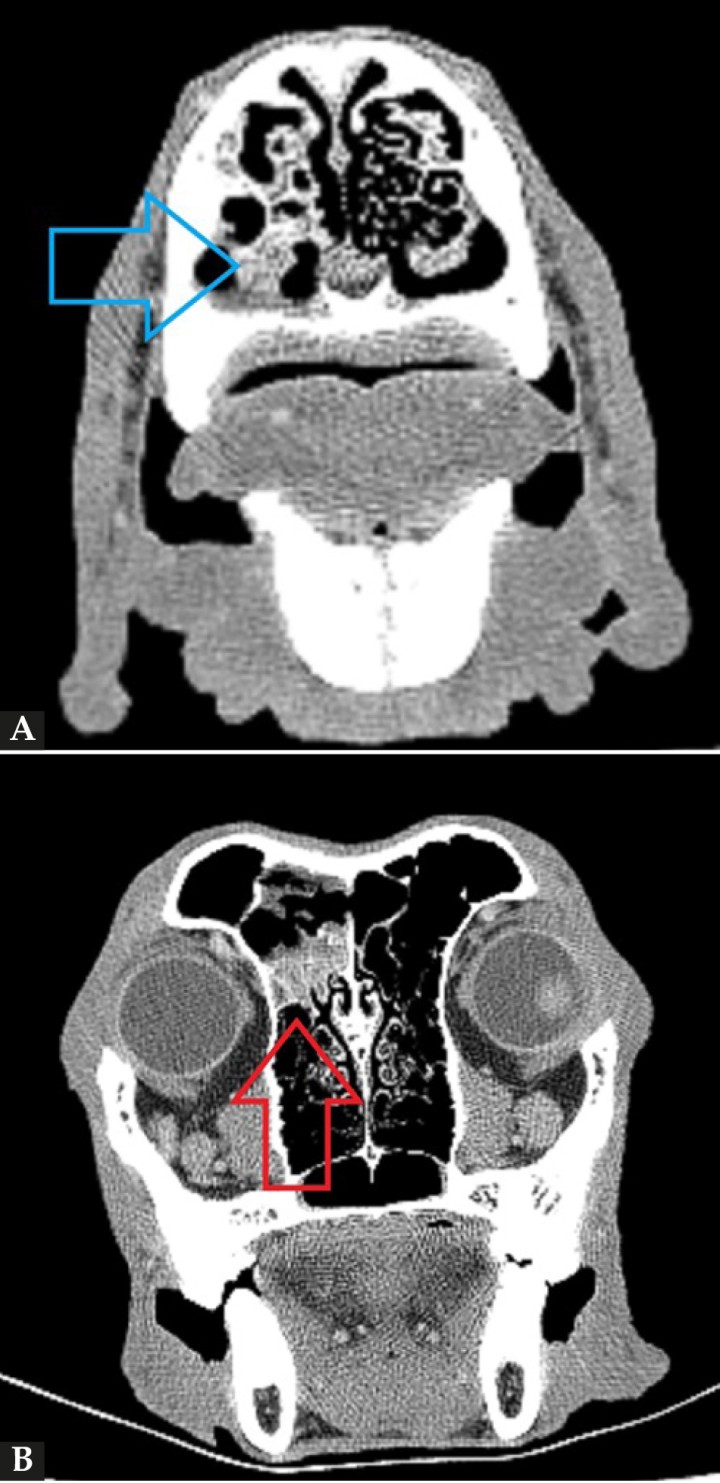

Se procedió a realizar una TC de cráneo (posicionamiento en recumbencia esternal, con 1,25 mm de corte, adquiriendo imágenes pre y postcontraste con contraste yodado Iohexol (Omnipaque 300 mg/ml, GE Healthcare Bio-Sciences, Florida) 400 mg/kg, con algoritmo de reconstrucción de tejido blando y hueso, General Electrics Healthcare, 4 cortes, España, Madrid). En la TC se observó en la cavidad nasal izquierda una moderada destrucción de turbinetes nasales con severo engrosamiento de la mucosa nasal y presencia de tejido blando anómalo (Fig. 1A), sin presencia de masas o cuerpos extraños, ni afectación de la lámina cribiforme. Dichas lesiones se extendían al seno frontal izquierdo (Fig. 1B). A continuación, se realizó una rinoscopia (fibroscopio 5,9 mm, FujiFilm, España, Madrid) donde se observó en la cavidad nasal izquierda múltiples placas de color blanquecino con aspecto caseoso/algodonoso adheridas a la mucosa nasal con eritema y congestión asociados (Fig. 2), junto a la destrucción moderada de los turbinetes, mostrando un aspecto cavitado. La cavidad nasal derecha no presentó alteraciones. Se tomaron muestras de tejido (placa fúngica y mucosa adyacente) para cultivo y análisis histopatológico. En el cultivo se obtuvo un crecimiento de Aspergillus fumigatus, y en los resultados de la biopsia de la placa fúngica se observó un tejido eosinofílico con abundantes hifas septadas, mientras que en el tejido adyacente se evidenció una mucosa erosionada y ulcerada con abundantes neutrófilos y macrófagos con hifas fúngicas esporádicas.

(A) Imagen de la TC de cráneo (región nasal, corte transversal en ventana de hueso postcontraste). Se observa una diferencia evidente entre la cavidad nasal derecha e izquierda, con moderada pérdida y destrucción de los turbinetes junto al engrosamiento de la mucosa y la presencia de tejido blando anómalo de la cavidad nasal izquierda (flecha azul). (B) Imagen de la TC de cráneo (región frontoorbitaria, corte transversal en ventana de hueso postcontraste). Se evidencia la presencia de engrosamiento de la mucosa y de tejido blando anómalo ubicado en el seno frontal izquierdo (flecha roja).

Los hallazgos más comunes de la TC son la destrucción de los cornetes nasales y ausencia del laberinto etmoidal, junto a la presencia de tejido blando anómalo y engrosamiento de la mucosa adyacente, pudiendo extenderse a los senos (72-74 %). En casos graves puede presentar reacción ósea y lisis de la lámina cribiforme.[ Billen F, Peeters D: Canine aspergillosis. En Ettinger SJ, Feldman EC, Cote E (8th): Textbook of Veterinary Internal Medicine. Misouri, Saunders Elsevier, 2017: 1035-1039. , Sharman MJ, Mansfield CS. Sinonasal aspergilosis in dogs: a review. Small Anim Pract 2012; 53(8): 434-44. [PubMed] ] Estas lesiones no son específicas, pudiendo presentarse hallazgos similares en otras patologías (p. ej., rinitis linfoplasmocitaria).[ Sharman MJ, Mansfield CS. Sinonasal aspergilosis in dogs: a review. Small Anim Pract 2012; 53(8): 434-44. [PubMed] ] La TC también permite valorar la presencia de causas predisponentes (cuerpos extraños, neoplasias, fracturas), además de la afectación de los senos y la presencia de afectación de la lámina cribiforme.[ Billen F, Peeters D: Canine aspergillosis. En Ettinger SJ, Feldman EC, Cote E (8th): Textbook of Veterinary Internal Medicine. Misouri, Saunders Elsevier, 2017: 1035-1039. , Sharman MJ, Mansfield CS. Sinonasal aspergilosis in dogs: a review. Small Anim Pract 2012; 53(8): 434-44. [PubMed] , Peeters D, Clercx C. Update on canine sinonasal aspergillosis. Vet Clin Small Anim 2007; 37: 901-916. [PubMed] ] En el presente caso se observaron alteraciones compatibles, llegando a afectar al seno frontal izquierdo, pero no presentaba una severa destrucción de los cornetes ni afectación de la lámina; posiblemente, la enfermedad estuviera en una fase temprana.